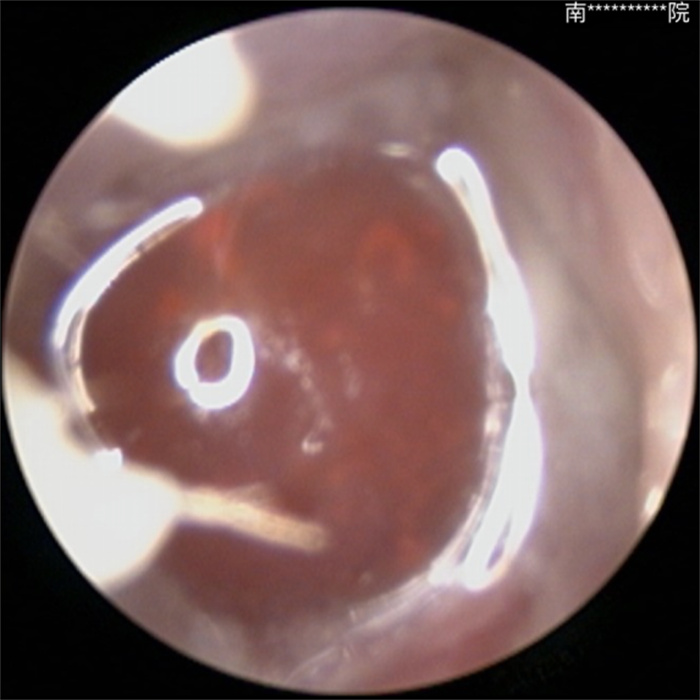

▲術(shù)前鼻內(nèi)鏡檢查圖像(紅色中央“水寶寶”)

在我院耳鼻咽喉頭頸外科就診時經(jīng)內(nèi)鏡檢查后,醫(yī)生發(fā)現(xiàn)其鼻腔內(nèi)竟藏有一顆膨脹的“水寶寶”(吸水樹脂玩具珠),周圍已形成大量肉芽組織并侵襲鼻軟骨。最終,患兒在全麻下接受鼻腔異物取出術(shù),術(shù)后恢復(fù)良好。